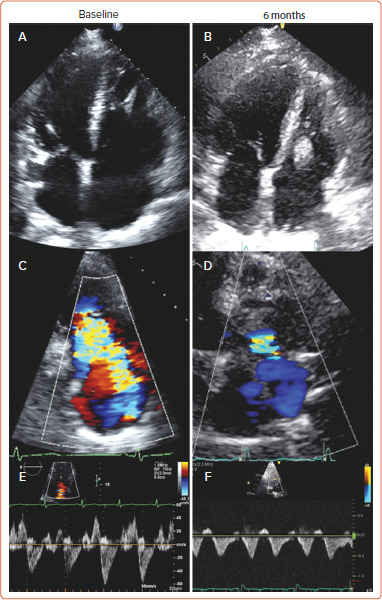

Abstract Image